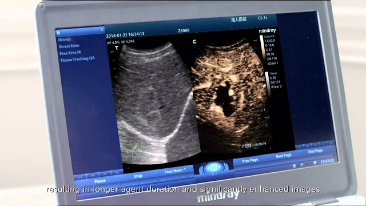

3T-Einkristall-Schallkopftechnologie

F├╝r sch?rfere Bilder sind alle mit dem M9 kompatiblen Sonden mit Mindrays einzigartiger 3T-Schallkopftechnologie ausgestattet. Das durch die Einkristalltechnologie verbesserte M9 bietet bessere Penetration und dynamischen Farbfluss, insbesondere bei der Untersuchung schwieriger Patientinnen oder Patienten.

Die Gewebe-Tracking- und quantitative-Analyse-Funktionalit?t des M9 bietet eine nicht-invasive L?sung zur einfachen und schnellen Bewertung von Anomalien der linksventrikul?ren Wandbewegung. Unterst├╝tzt durch Mindrays patentierte 3T-Einkristall-Technologie, verbessert das M9 die Trackinggenauigkeit und ?wirksamkeit signifikant durch Kontrolle der durch die Sondenbewegung und das Atmen verursachten Bilddrift. Angesichts des einzigartigen Vorteils der neu hinzugef├╝gten Vor-Ort-Analyse kann die TT QA mit dem M9 am Krankenbett durchgef├╝hrt werden, was zeitsparend ist und komplizierte Diagnosen deutlich einfacher macht.